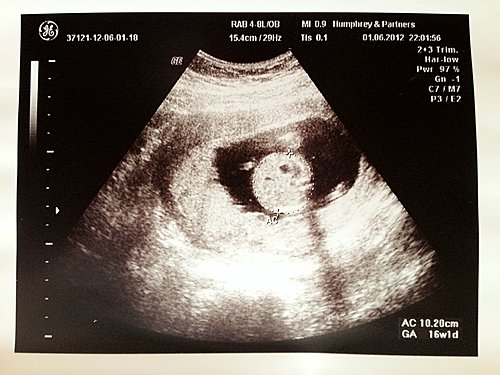

隔咗 4 個星期,阿 B 大咗幾多呢~ 我哋睇佢的時候,佢仲係度不斷郁來郁去,又係度食手指仔~

而阿 B 的頭圍、肚圍同埋大脾骨都係符合週數的,靳醫生叫我哋唔駛擔心,而靳醫生呢次幫我哋照多次阿 B 的性別,仲話 8 成係 B 女來的,唔知點解呢我聽到後又無乜嘢,仲有 d 開心,因為可以 B 女的衫仔靚好多嫁,我可以開始買 BB 衫,幫 B 女扮靚靚呢~